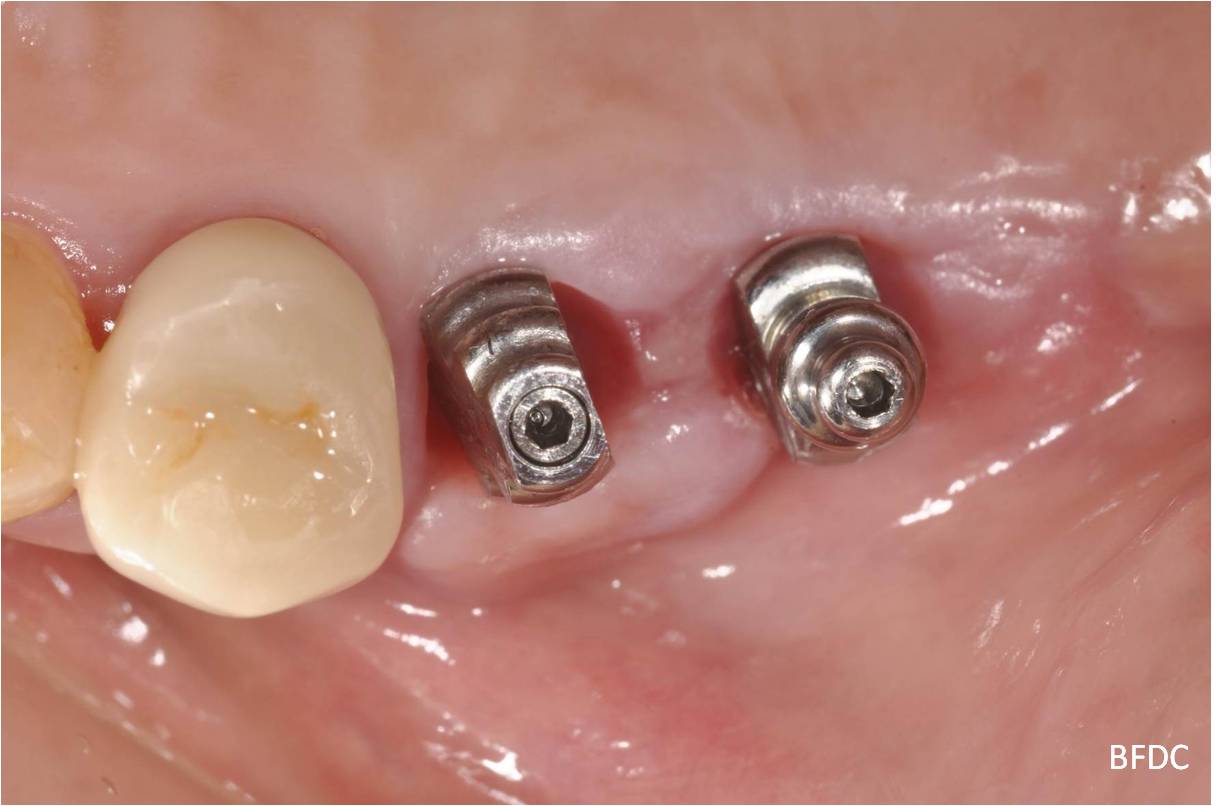

植體二段式假牙口內套件

植牙印模